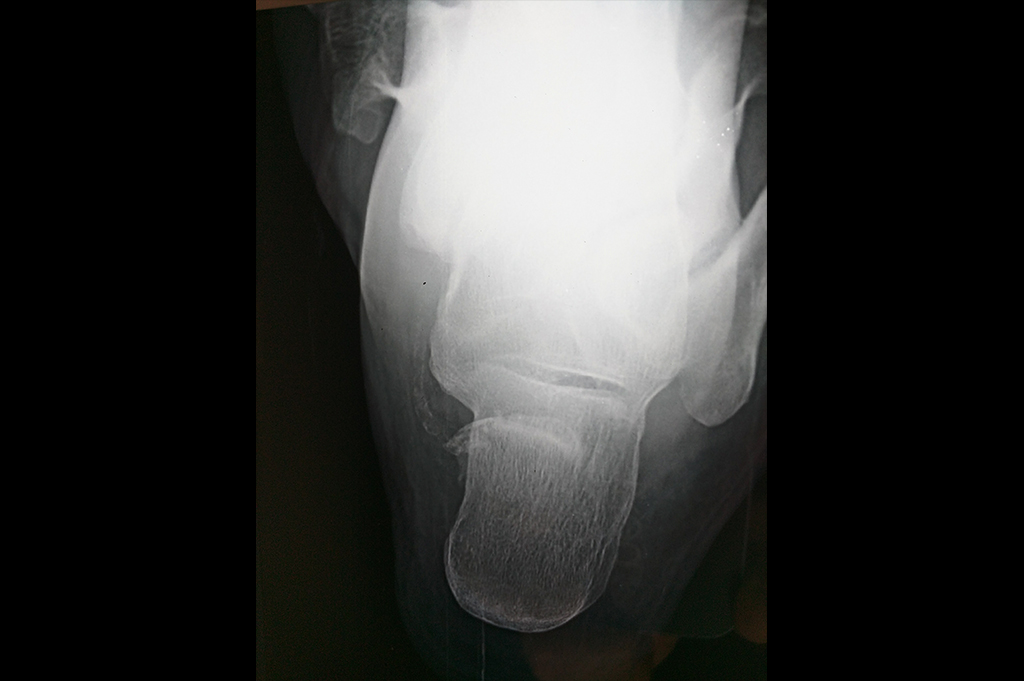

Calcaneum